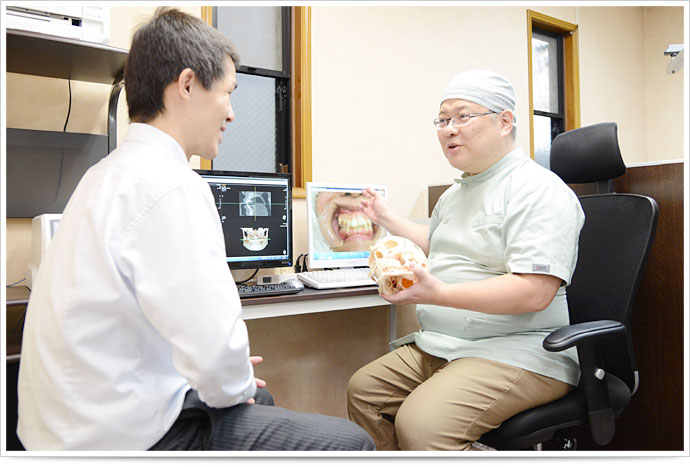

当院では、そのような不安を解消すべく、精密機器による科学的根拠に基づいた矯正治療を実践しています。下記に、当院の矯正治療の特徴をご紹介いたします。

当院では、従来のような「人の感覚」に頼っていた咬み合わせの診査診断ではなく、咬み合わせ機能分析装置による診査診断システムを導入しております。このシステムの導入により、従来は困難とされていた「顎の動き」や「咬み合わせ位置・力」を測定することが可能となりました。

精密検査の結果をもとに、矯正治療全般に関して詳しくご説明をいたします。

少しでも疑問点がございましたら、再度ご説明し納得いただいたうえで、治療を開始するかどうかのお返事をいただきます。もちろん、この段階で治療を受けないという選択をしていただいても全く構いません。